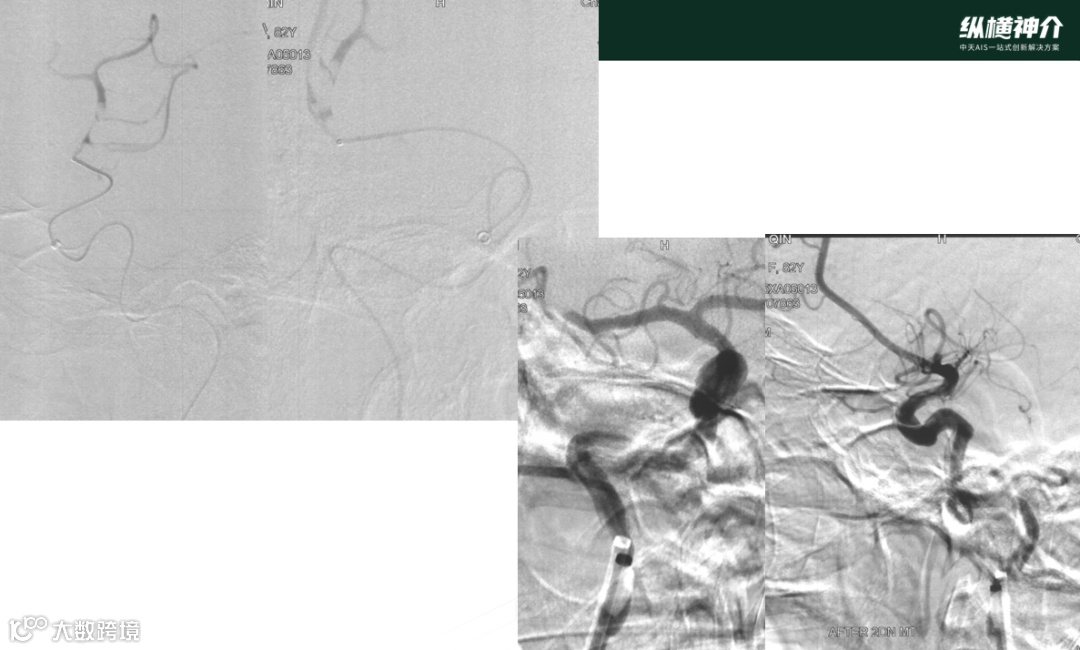

病例二

• 天弋®取栓支架 6*40mm 4*30mm

• 微导管在到达远端后,造影发现M2处也有血栓存在

• 天弋® 6*40mm取栓支架到位释放打开,显影性非常好,相比其他尺寸,对大负荷量血栓具有优势

• 天弋®取栓支架从近端到远端是缠绕血栓,而没有被近端血栓刮除掉

• 二次取栓操作,大脑中和颈内动脉血栓进一步减容